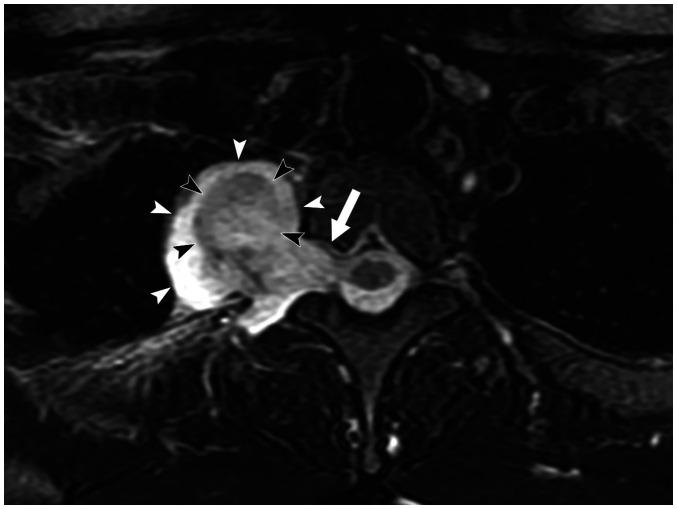

Magnetic resonance imaging (MRI) has become a crucial tool for evaluating mediastinal masses considering that several lesions that appear indeterminate on computed tomography and radiography can be differentiated on MRI. Using a three-compartment model to localize the mass and employing a basic knowledge of MRI, radiologists can easily diagnose mediastinal masses. Here, we review the use of MRI in evaluating mediastinal masses and present the images of various mediastinal masses categorized using the International Thymic Malignancy Interest Group's three-compartment classification system. These masses include thymic hyperplasia, thymic cyst, pericardial cyst, thymoma, mediastinal hemangioma, lymphoma, mature teratoma, bronchogenic cyst, esophageal duplication cyst, mediastinal thyroid carcinoma originating from ectopic thyroid tissue, mediastinal liposarcoma, mediastinal pancreatic pseudocyst, neurogenic tumor, meningocele, and plasmacytoma.

磁共振成像(MRI)已成为评估纵隔肿块的重要工具,因为 CT 和 X 线摄影上表现为不确定的一些病变可以在 MRI 上区分。使用三室模型定位肿块并运用 MRI 的基本知识,放射科医生可以轻松诊断纵隔肿块。在这里,我们回顾了 MRI 在评估纵隔肿块中的应用,并展示了使用国际胸内恶性肿瘤兴趣小组的三室分类系统对各种纵隔肿块进行分类的图像。这些肿块包括胸腺增生、胸腺囊肿、心包囊肿、胸腺瘤、纵隔血管瘤、淋巴瘤、成熟畸胎瘤、支气管囊肿、食管重复囊肿、起源于异位甲状腺组织的纵隔甲状腺癌、纵隔脂肪肉瘤、纵隔胰腺假性囊肿、神经源性肿瘤、脑脊膜膨出和浆细胞瘤。